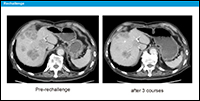

最後に、当院で抗EGFR抗体薬のre-challengeを受けた症例を紹介します。88歳の男性で、S状結腸癌です。抗EGFR抗体薬併用治療9サイクル後に最大の腫瘍縮小が認められましたが、11サイクル後に増悪が認められました。以降、化学療法は中止されていましたが、その後腫瘍の急速な増悪に対し抗EGFR対抗薬を再投与したところ、腫瘍縮小効果が認められました (図12)。